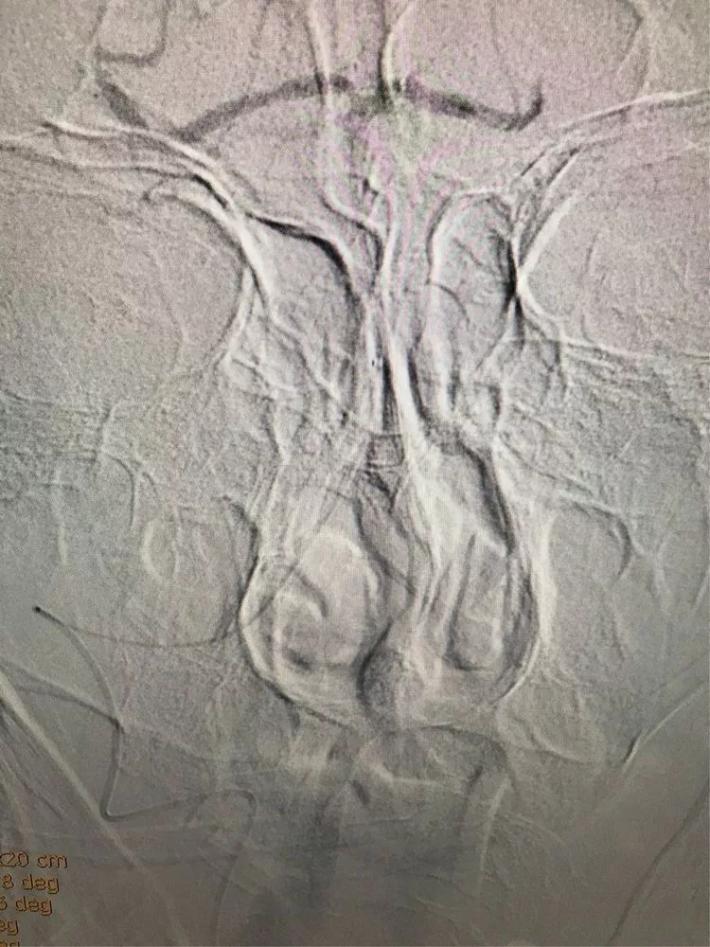

立即桥接取栓,造影显示:左侧颈内动脉闭塞。

右侧颈内动脉向左侧没有代偿。

椎动脉造影显示后交通动脉没有代偿。

微导管进入左侧大脑中动脉远端真腔。

置入支架。

可见大脑中动脉有血流。

取出支架未见血管开通。

再次置入微导管。

置入支架取栓。

见颈内动脉开通,大脑中动脉远端有血栓逃逸。